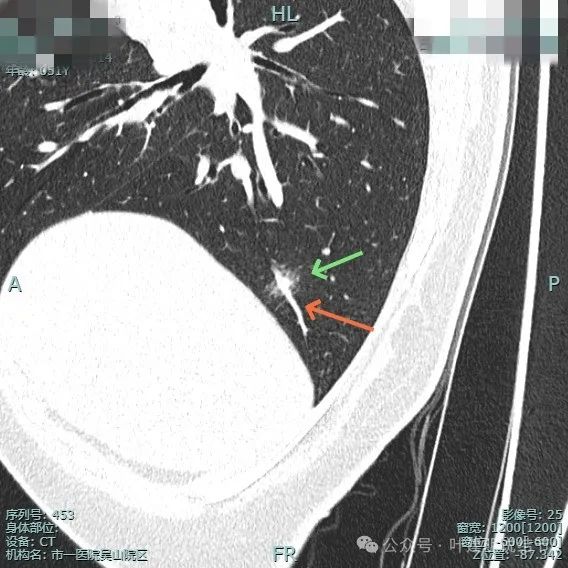

靶重建显示边缘细毛刺、外围磨玻璃密度,中间实性成分明显,表面不平有浅分叶。

中间实性成分感觉边缘较清,缺乏收缩力,外围的磨玻璃成分整体轮廓较清,边缘有细毛刺征。

明显的血管进入与异常增粗。

灶内密度杂乱,血管进入与增粗,表面不平。

实性成分明显,但缺乏收缩力;边上是磨玻璃成分,整体轮廓较清;邻近血管走行,但没有形成血管弯征。

边缘细毛刺,不太锐利;外围磨玻璃成分,瘤肺界限欠清;中间实性成分明显但缺乏收缩力,实性部分没有明显毛刺征。

血管进入与异常增粗并散开来(在肿瘤性病变中,这种表现是浸润性而且风险大的表现)。

血管进入穿行并异常增粗,磨玻璃成分显得较为散在,缺乏聚拢性。